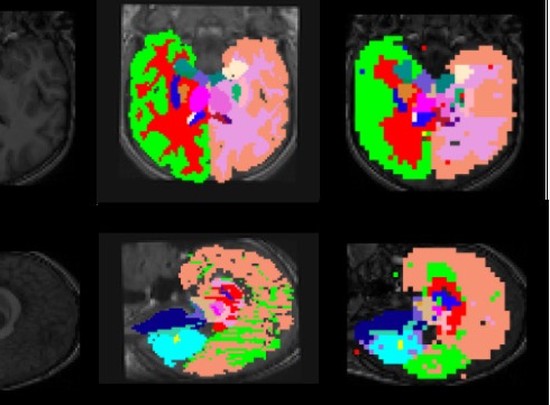

New Deep Neural Network stucture for 3D Medical Image Segmentation